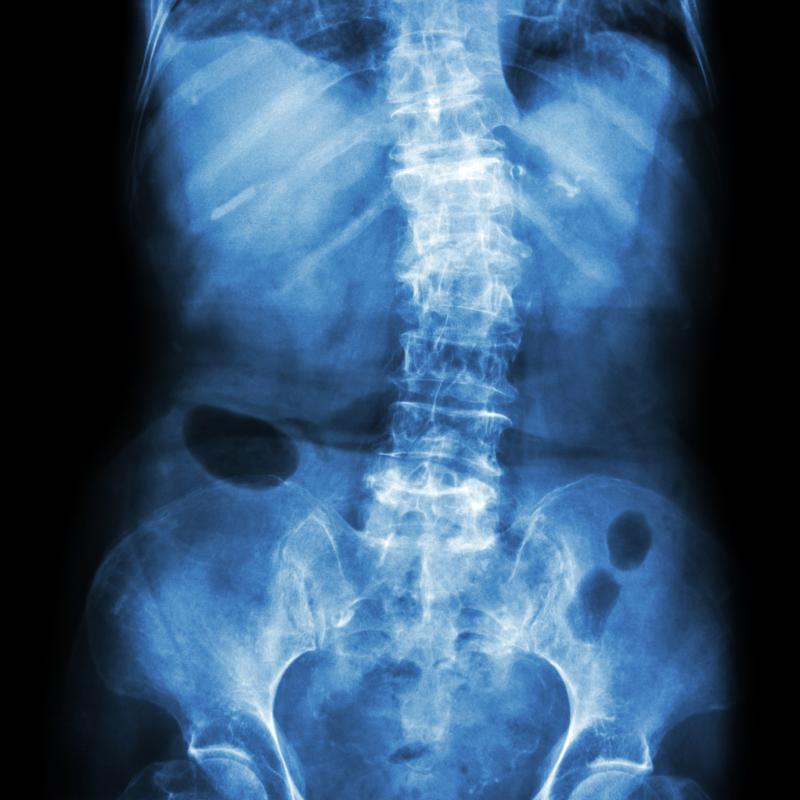

Smartphone-based real-life activity data can be used to track physical performance in patients after lumbar spine surgery for degenerative lumbar disorders (DLD), according to a recent study.